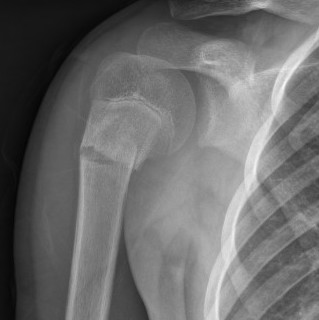

Snapping scapula

Definition

Disruption of the normal smooth motion of the scapulothoracic joint

- posterior scapula pain with overhead motion

Etiology

1. Bony abnormalities

- osteochondromas

- prominence of the superior medial border of the scapula / Luschka tubercle

2. Soft tissue abnormalities

- bursitis / scar tissue

- muscular weakness

3. Masses